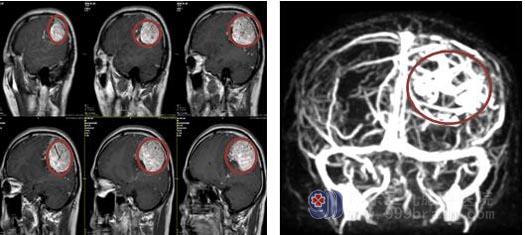

叶大叔来到广东三九脑科医院神经外五科后,主管医生对他进行了全面细致的检查。头颅MRI显示:左侧顶部占位性病变伴病灶内及周围多发畸形血管,范围约5.5cm×6.0cm×6.4cm,考虑脑膜瘤可能性大。

▲肿瘤及肿瘤引流血管

医院副院长、神经外五科主任鲁明认为,叶先生的颅顶部肿瘤体积大,有可能合并动静脉畸形,手术难度高,风险极大,术中可能大量出血,直接影响患者的生命安全。经过科室医生团队详细分析讨论后,决定先行全脑血管造影术,明确肿瘤是否合并动静脉畸形,同时了解肿瘤具体的供血血管,如果肿瘤合并动静脉畸形,可行动静脉畸形栓塞术,再行肿瘤切除;如无动静脉畸形,则可行肿瘤主要供血动脉栓塞术,减少肿瘤血供,再行肿瘤切除术。设计好最佳手术方案并经家属同意后,行全脑血管造影术,术中发现有左侧颞浅动脉、枕动脉、大脑中动脉、大脑后动脉及右侧颞浅动脉、枕动脉6支较大血管供血,予以行介入栓塞术,选择性栓塞4支供血血管。